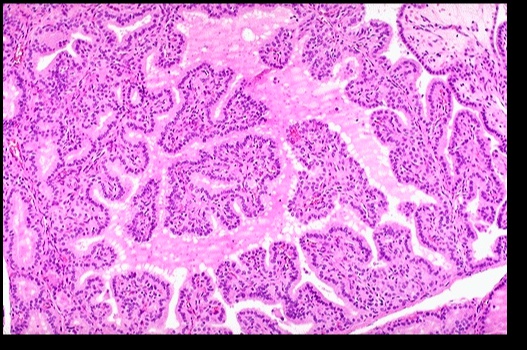

_Histologically, defined by:

Lymphocytic infiltrate (germinal centers)

Atrophic thyroid follices lined by Hürthle cells (pink epithelial cells).,

Chronic inflammation, germinal centers and Hurthle cells:

_Because thyroid follicles are normally lined by low cuboidal epithelium, this is also known as Hürthle cell metaplasia.,

_On histology, a lymphocytic infiltrate with multinucleated giant cells surround fragments of colloid.

.,Subacute granulomatous thyroiditis. Note the giant cells, inflammatory cells and destruction of the thyroid follicules.

_On histology, appears with lymphocytic infiltrate and prominent germinal follicles. Hürthle cell metaplasia is not prominent (versus Hashimoto thyroiditis, in which Hürthle cell metaplasia is a prominent feature).

.,Lymphcytic inflitrate seen in subacute lymphocytic thyroiditis.